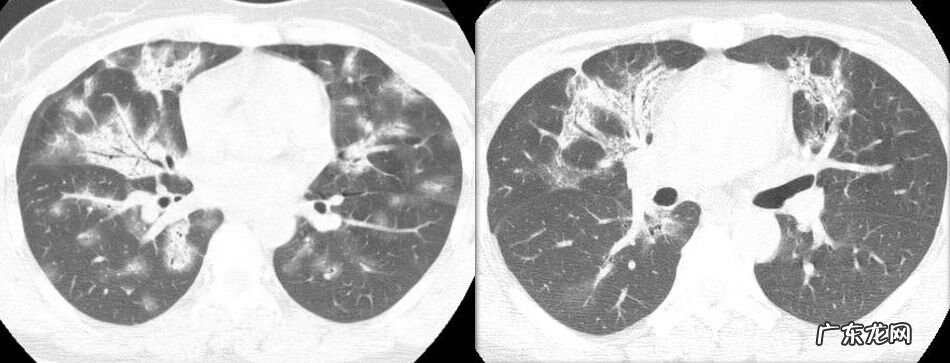

看到多发斑片状实变影的时候,除了OP,如果没有临床症状,我们需要和哪些疾病鉴别?

VS 淋巴瘤

淋巴瘤也可以出现这样的实变影,但常伴多发结节影;病灶多位于中内带,但OP的病灶在外带多见;除了肺内的病灶,还有纵膈淋巴结肿大融合 。

VS 急性嗜酸粒细胞性肺炎

急性嗜酸粒细胞性肺炎(AEP)也可以出现双肺多发斑片状实变影,如果单从影像上来看,支气管充气征较OP少见,支气管扩张罕见,另外,中上肺外带为主,病灶边界不清 。影像上鉴别比较困难,但是AEP多有哮喘病史,低氧导致的呼吸困难较为明显,血或支气管灌洗液嗜酸性粒细胞比例增高可以提示大家 。